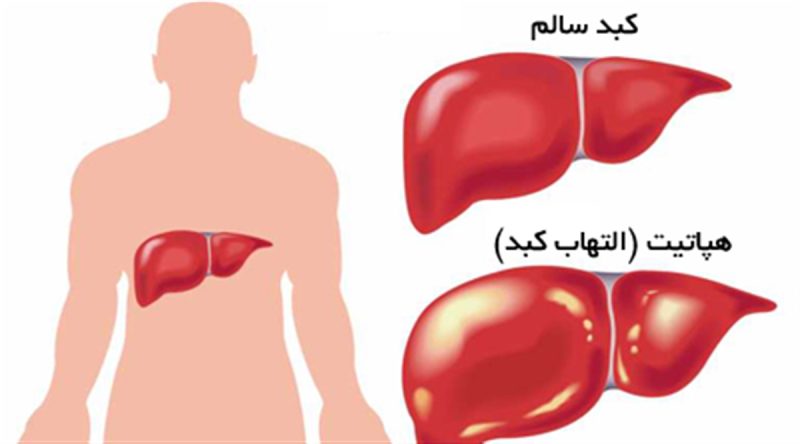

هپاتیت یعنی التهاب کبد و در میان عوام مردم به یرقان و زردی مشهور است. مهمترین عوامل ایجاد کننده آن ویروسها هستند. ویروسها موجودات بسیار ریزی هستند که از فرد آلوده به فرد سالم منتقل می شوند وبرای رشد وتکثیر خودبه یک موجود زنده نیاز دارند.

هپاتیت مزمن: اگر بیماری پس از 6 ماه بهبود نیاید به آن « هپاتیت مزمن» گفته می شود که شایع ترین عارضه است. در 75درصد موارد هپاتیت B یا C عامل آن بوده و معمولاً با درمان مناسب طی 1 تا 3 سال درمان می شود.